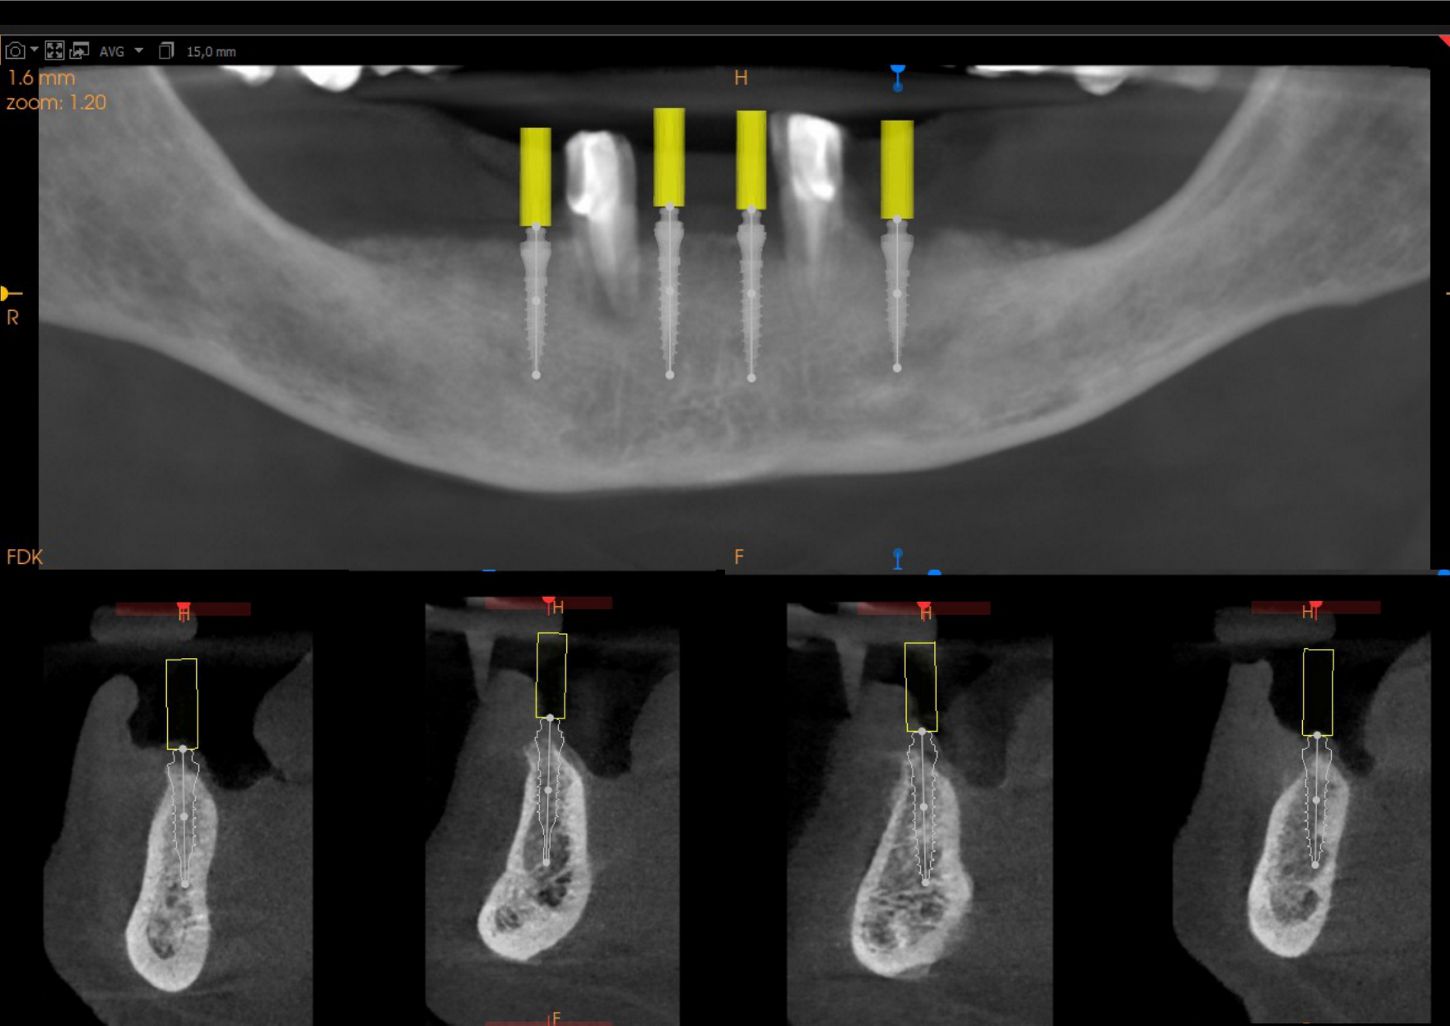

1a. 1b. Pre-operative panoramic X-ray and CBCT showing moderate generalised bone resorption in the mandible, a reduction in vertical dimension in the posterior region and the planned positioning of mini- implants.

1a

1b